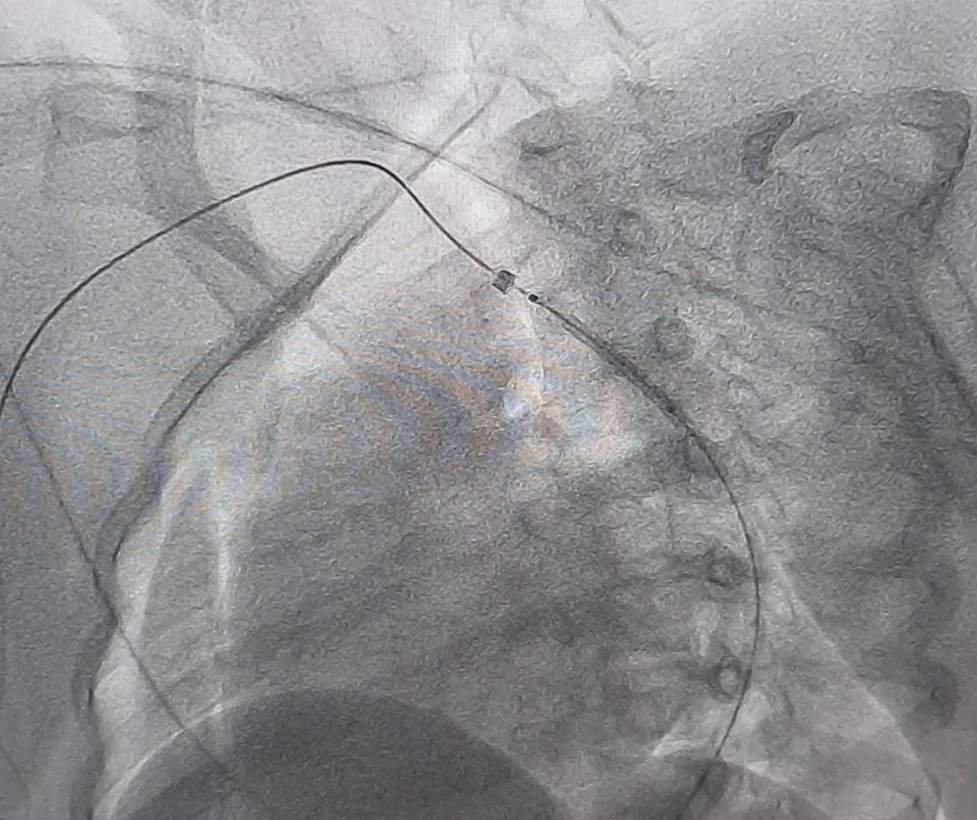

Врожденный порок сосуды у нее был ликвидирован специалистами с помощью малоинвазивной эндоваскулярной процедуры - установление стента в просвет сосуда. Результат лечения медики довольны. Впоследствии у ребенка нормализовались соответствующие показатели артериального давления, а его разница между верхними и нижними конечностями исчезла.

У пациентки при обследовании обнаружили врожденный порок сердца - коарктацию аорты. Это состояние, при котором фиксируется имеется сужение просвета аорты, вследствие чего развивается повышенное давление в верхней половине тела.